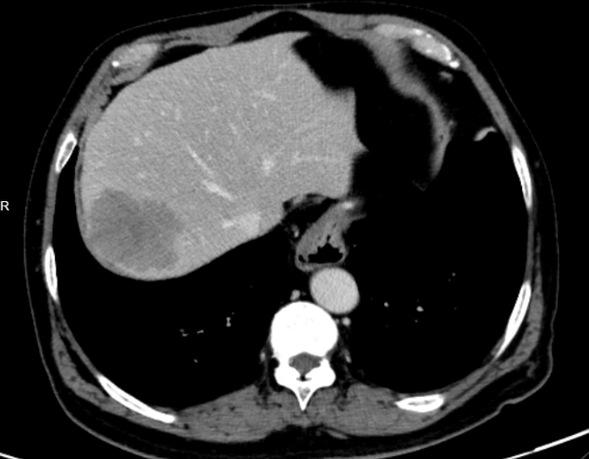

赵某,男,69岁,2年前行结肠癌根治术,病理回报:(乙状结肠)溃疡型中分化腺癌(体积:3*3*2cm),浸至外膜,上、下切缘、环周切缘未见癌,肠周淋巴结可见转移癌(5/8)。后续静脉化疗6疗程,病情控制稳定。近日,行上腹增强CT检查提示:肝继发恶性肿瘤。这一消息犹如晴天霹雳,“刚刚治好这个肿瘤,怎么又有肿瘤了?”老赵经过多方打听与了解来到我院介入科寻求治病良方。

初发病灶CT